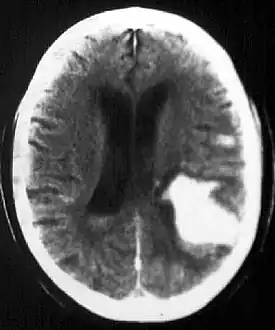

CT scan shows a very large intraparenchymal haemorrhage with mass effect and occupying most of the right frontal lobe -

Intraparenchymal hemorrhage -

CT-scan of intraparenchymal hemorrhage

Computed tomography (CT scan): A CT scan may be normal if it is done soon after the onset of symptoms. A CT scan is the best test to look for bleeding in or around your brain. In some hospitals, a perfusion CT scan may be done to see where the blood is flowing and not flowing in your brain.